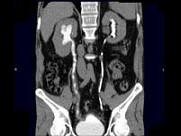

- 多项选择题男,47岁, 腰痛、腰胀2月余伴低热、乏力,结合影像资料所示, 下列哪项说法正确 ( )

A、右侧输尿管多发性狭窄,呈“串珠样”改变

B、右侧输尿管多发性生理性狭窄

C、右侧肾盂轻度积水

D、考虑为右输尿管占位病变

E、考虑为右输尿管结核